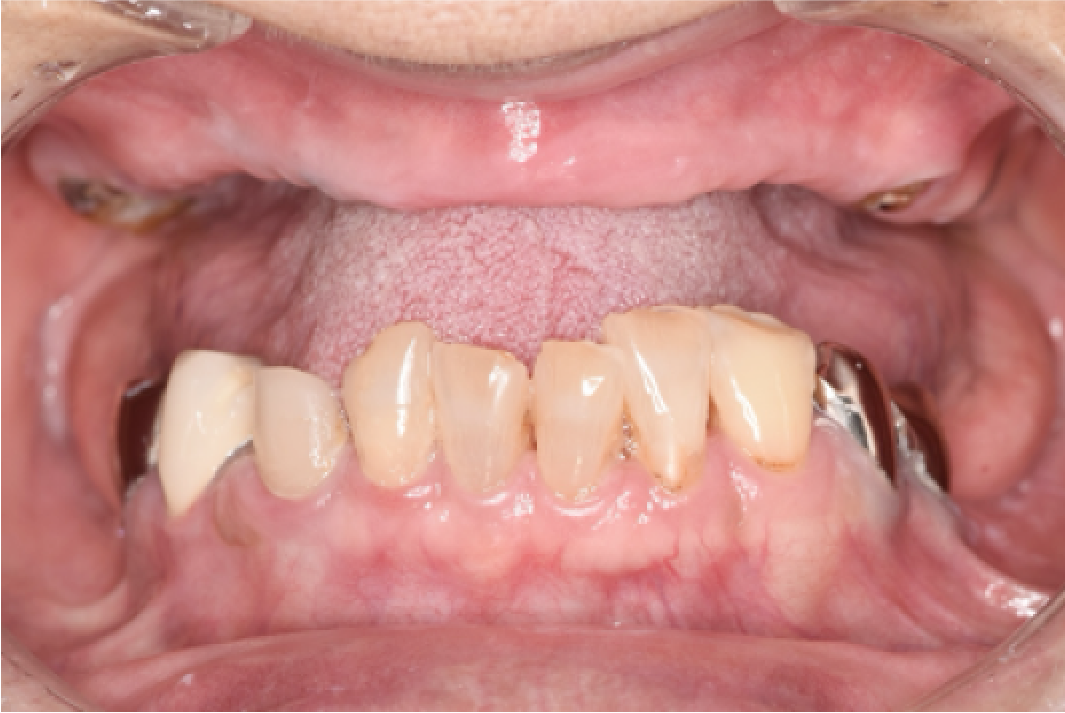

CASE04

■ 治療内容

上下顎All-on-4インプラント治療

■ 治療費用

6,627,000円(税込)

■ 治療期間

約9ヶ月

■ リスク

治療後の腫れや出血、またメンテナンスを怠ることで周囲炎のリスクあります。